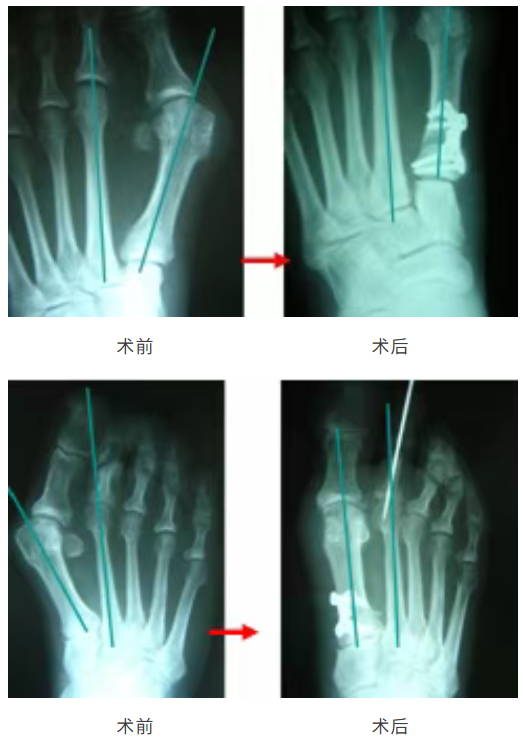

臨床應用病(bing)例(li)

楔形鎖定板

型號(hao):DGB07

楔形高(gao)度(du):0/2/3/4/5/6/7mm